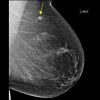

Ung thư vú

Ung thư vú - Ảnh 2

Ung thư vú - Ảnh 3

Ung thư vú - Ảnh 4

Ung thư vú - Ảnh 5

» Thông tin: Nữ giới – 71 tuổi.

» Lâm sàng: Khối tuyến vú.